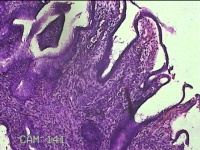

宫颈6点外缘、9点组织

性别

女

年龄

18岁

临床诊断

宫颈炎性疾病

一般病史

宫颈高危HPV感染

标本名称

大体所见

1.“宫颈6点外缘组织”:灰白粉红色不规则组织0.7x0.5x0.3cm两块。 2.“宫颈9点组织”:灰白粉红色不规则组织0.5x0.3x0.2cm一块。

良性病变。